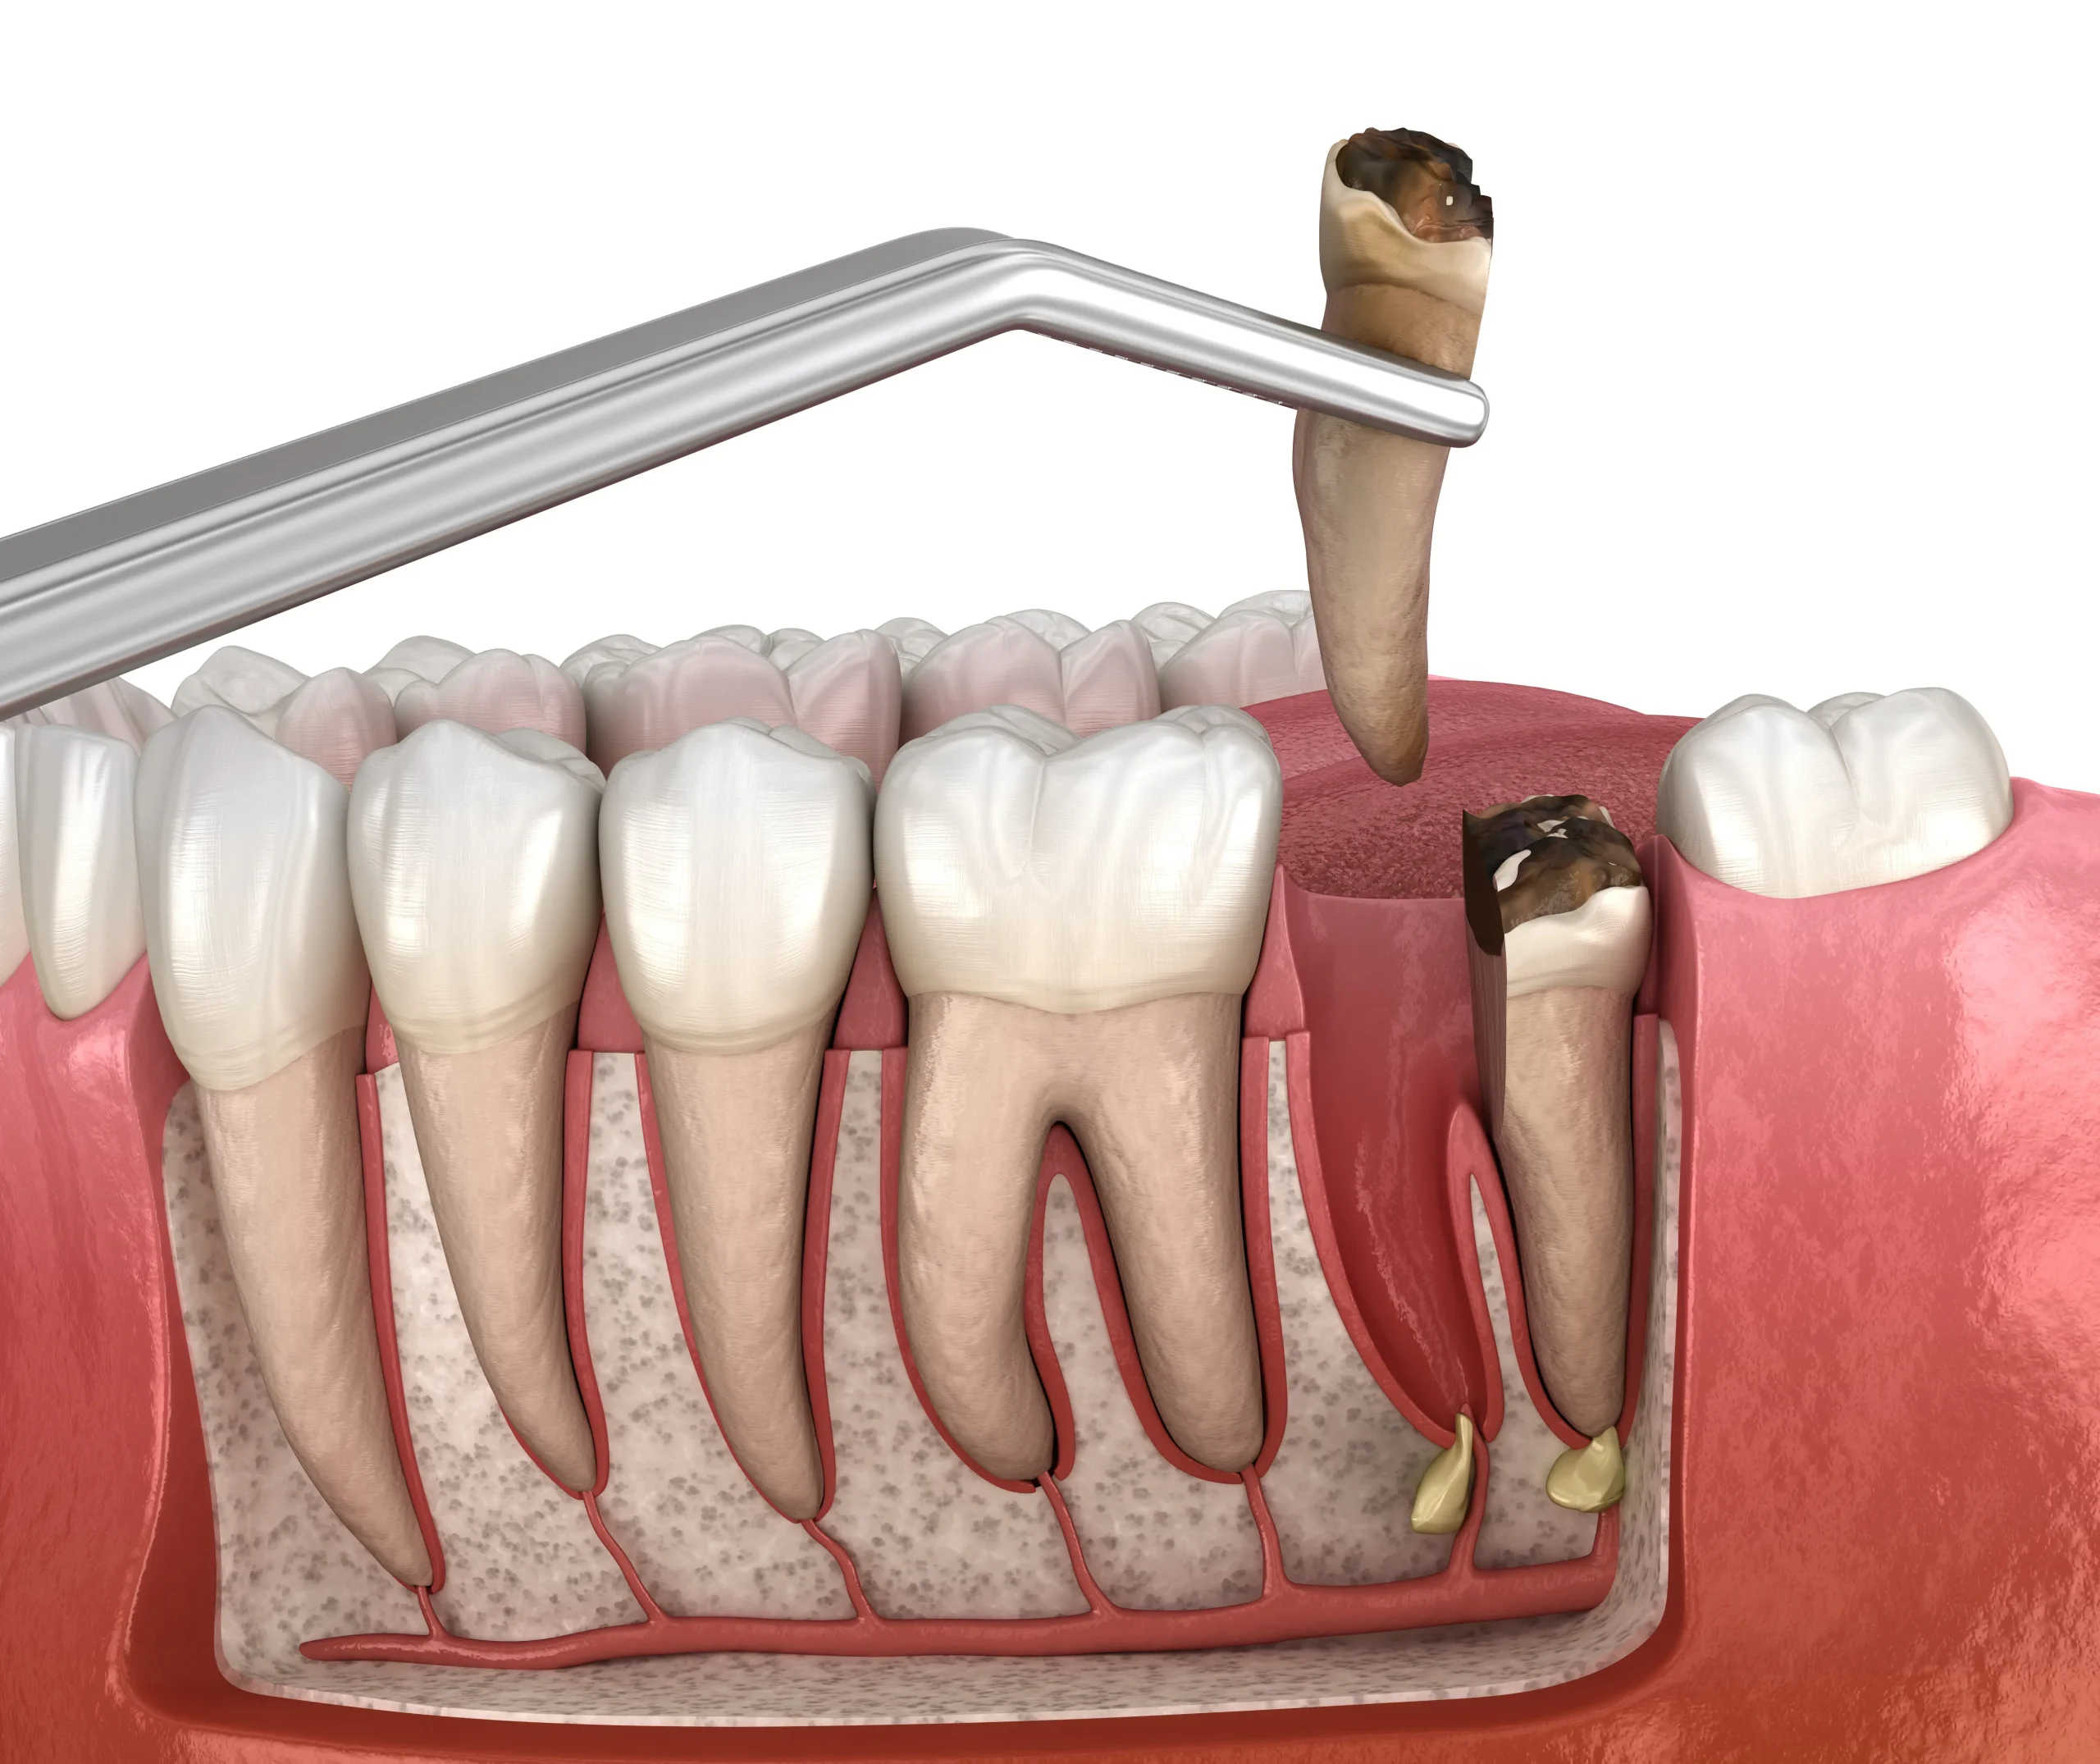

Done when a previously treated tooth develops new infection or was not fully healed the first time.

A minor surgical procedure to remove the tip of the root when standard RCT isn’t sufficient.